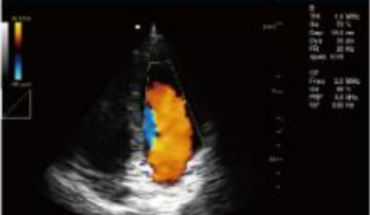

- B+CF (Dual Images)

- B+CF/DPDI+PW (Triplex)